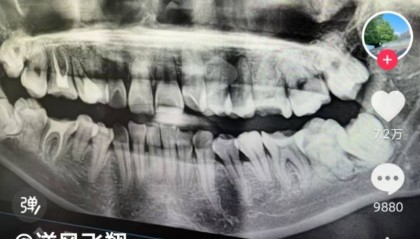

安徽一女子被拔错牙后坠楼身亡,家属:好牙位置没打麻药,硬生生拔下来